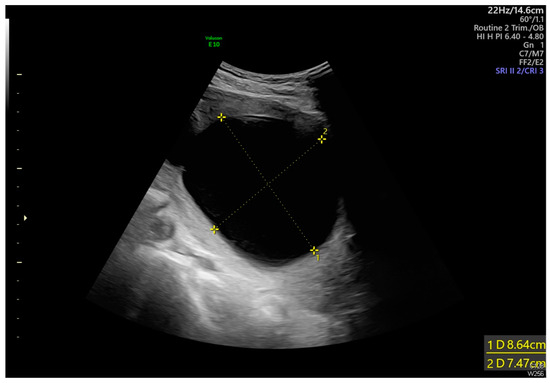

Intrauterine Adhesion-Induced Septated Amniotic Cavity: Ultrasonographic Findings in Second and Third Trimesters

Huang, J.-T.; Chen, Y.-M.; Tsai, C.-C.; Cheng, H.-H.; Lai, Y.-J.; Lee, P.-F.; Hsu, T.-Y.; Huang, K.-L. Intrauterine Adhesion-Induced Septated Amniotic Cavity: Ultrasonographic Findings in Second and Third Trimesters. Diagnostics 2024, 14, 2826. https://doi.org/10.3390/diagnostics14242826